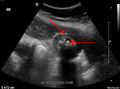

Imaging

Right upper quadrant abdominal ultrasound is most commonly used to diagnose cholecystitis.[1][25][26] Ultrasound findings suggestive of acute cholecystitis include gallstones, pericholecystic fluid (fluid surrounding the gallbladder), gallbladder wall thickening (wall thickness over 3 mm),[27] dilation of the bile duct, and sonographic Murphy's sign.[13] Given its higher sensitivity, hepatic iminodiacetic acid (HIDA) scan can be used if ultrasound is not diagnostic.[13][14] CT scan may also be used if complications such as perforation or gangrene are suspected.[14]

28. ^ a b "UOTW #30 - Ultrasound of the Week". Ultrasound of the Week. 23 December 2014. Archived from the original on 9 May 2017. Retrieved 27 May 2017.